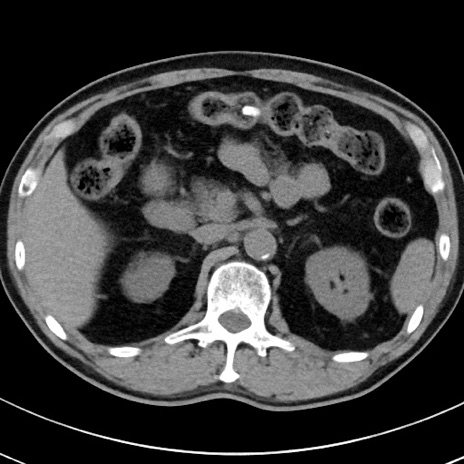

【腹部TIPS】症例29 参考症例 CT(横断像)

症例

70歳代男性